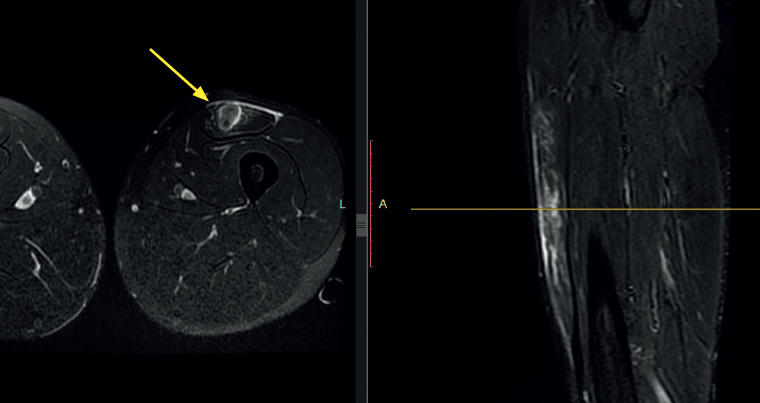

Figure 4. Magnetic resonance imaging scan of the left thigh in axial and sagittal view (T2). Bull's eye sign in a lesion of the left rectus femoris, causing edema around the central tendon and edema of the surrounding muscle tissue (yellow arrow).

In the case of injuries affecting the intramuscular tendon of the RF, the MRI study often evidences the so-called bull's eye sign, corresponding to an increase in signal intensity around the intramuscular tendon of the RF (Figure 4), that can evolve as the lesion matures from initial edema and bleeding to healing with increased vascularisation around the tendon. A bull's eye sign with atrophy and fat infiltration around the tendon corresponds to an old injury, and we occasionally may observe a pseudocyst due to serohematic fluid accumulation in the rupture zone(20), though this finding is more common in children than in adults.